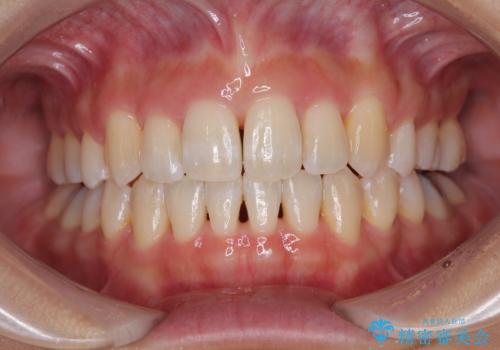

[ マウスピース矯正] 前歯のがたつき 出っ歯に見える歯をきれいに

![[ マウスピース矯正] 前歯のがたつき 出っ歯に見える歯をきれいに の症例 治療後](https://seimitsushinbi.jp/wp/wp-content/uploads/2025/04/a5c1eab0aff12598c7b5c9fb710c2648-500x350.jpg?v=1744960670)